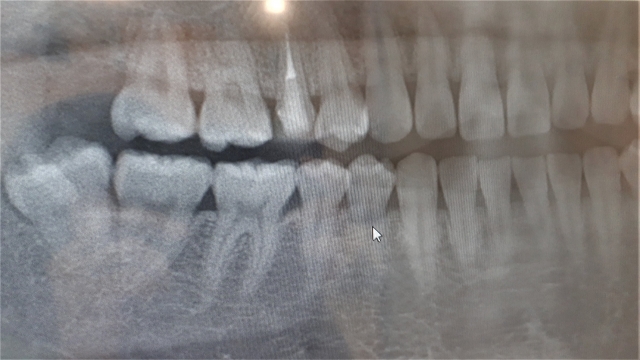

親知らずの抜歯が難しいとされる理由は、歯の位置や生え方、周囲の組織との関係にあります。親知らずは一番奥に生えるため、スペースが不足しやすく、まっすぐに生えないことが多いのが特徴です。横向きや斜めに埋まっている場合、歯ぐきを切開したり、歯を分割して取り出す必要があるため、処置の難易度が上がります。

さらに、下顎の親知らずでは、神経や血管が近接しているケースがあります。この神経に影響を与えないよう慎重に処置する必要があるため、より高度な技術と診断が求められます。また、骨の硬さや口の開き具合、炎症の有無なども影響します。

特に神経に近い場合は、事前にCT撮影などで位置関係を確認し、リスクを評価します。このような検査を行うことで、安全性を高めることが可能です。また、術後の過ごし方も重要であり、強いうがいや飲酒、激しい運動を控えることでトラブルを防ぐことができます。